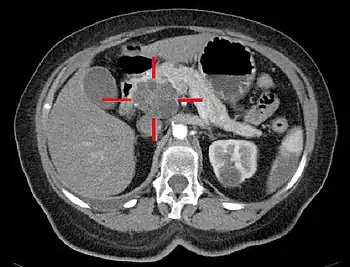

Imagerie

Elle vise à évaluer la taille et la localisation de la tumeur, et celles d'éventuelles métastases ganglionnaires, hépatiques, ou péritonéales.

On étudie également les rapports avec la veine porte.

Le scanner abdominal avec injection d'un produit de contraste iodé reste l'examen de référence. Il permet de mieux juger de l'extension locale et de l'existence de métastases, en particulier sur le foie et de juger ainsi de l'opérabilité[35].